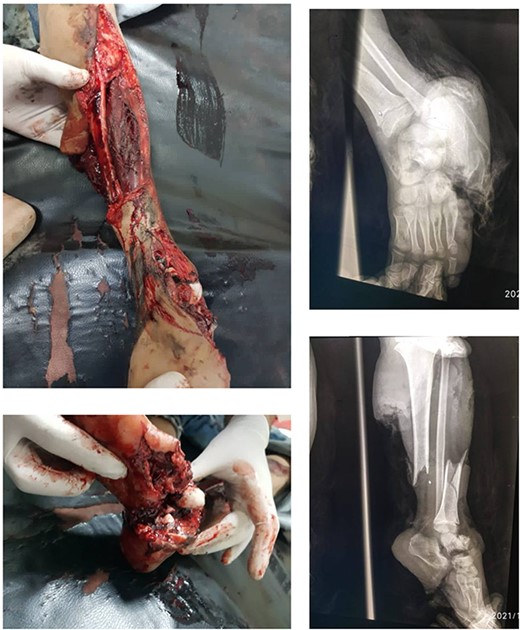

A 7-year-old boy experienced severe trauma to his left lower limb in a vehicular accident. At the emergency department, a comprehensive examination revealed a complex injury profile, including severe open fracture, dislocation of the subtalar joint and ankle, comminuted fracture of the cuboid with significant soft tissue loss, periosteal stripping, severe contamination, and lacerations in the posterior calf muscles. The limb was classified as Type III C according to the Gustilo-Anderson system, with no concurrent injuries noted in the systemic assessment except for the affected limb (Fig. 1). The initial vital signs were as follows: blood pressure, 90/60 mmHg; pulse rate 160/min, respiratory rate 40/min, and body temperature, 38°C. Neurological examination showed a Glasgow Coma Scale score of 15, except for a limb injury that caused sensation and movement loss. Admission tests showed leukocytosis (WBC 15.7), 85% neutrophils, and hemoglobin level of 8.5 g/dl. The wound was infected with Staphylococcus aureus and Pseudomonas species, requiring immediate antibiotic therapy based on sensitivity.

Displays the fractured image alongside the X-ray images taken prior to the intervention.